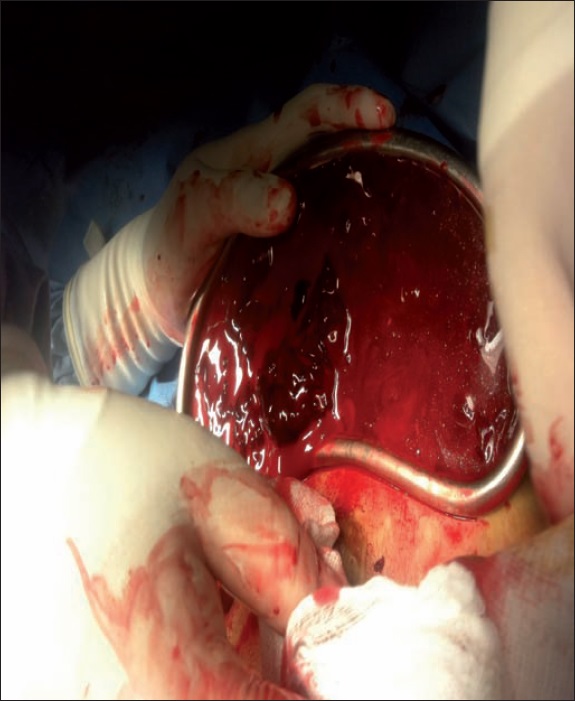

Realizamos abordaje quirúrgico a través de la incisión previa en el pliegue submamario derecho, drenando un hematoma de 1600cc. Retiramos el implante retromuscular sin dificultad y exploramos el lecho quirúrgico (Fig. 2 y 3). Al no localizar el punto de sangrado, optamos por ampliar la incisión submamaria hasta 12 cm y observamos sangrado activo de una rama muscular, 3 cm por debajo de la clavícula a nivel de la unión del 1/3 medio y el 1/3 externo; procedimos a su ligadura con seda 2-0 sin complicaciones, y corroboramos durante unos minutos que la hemostasia fuera adecuada.